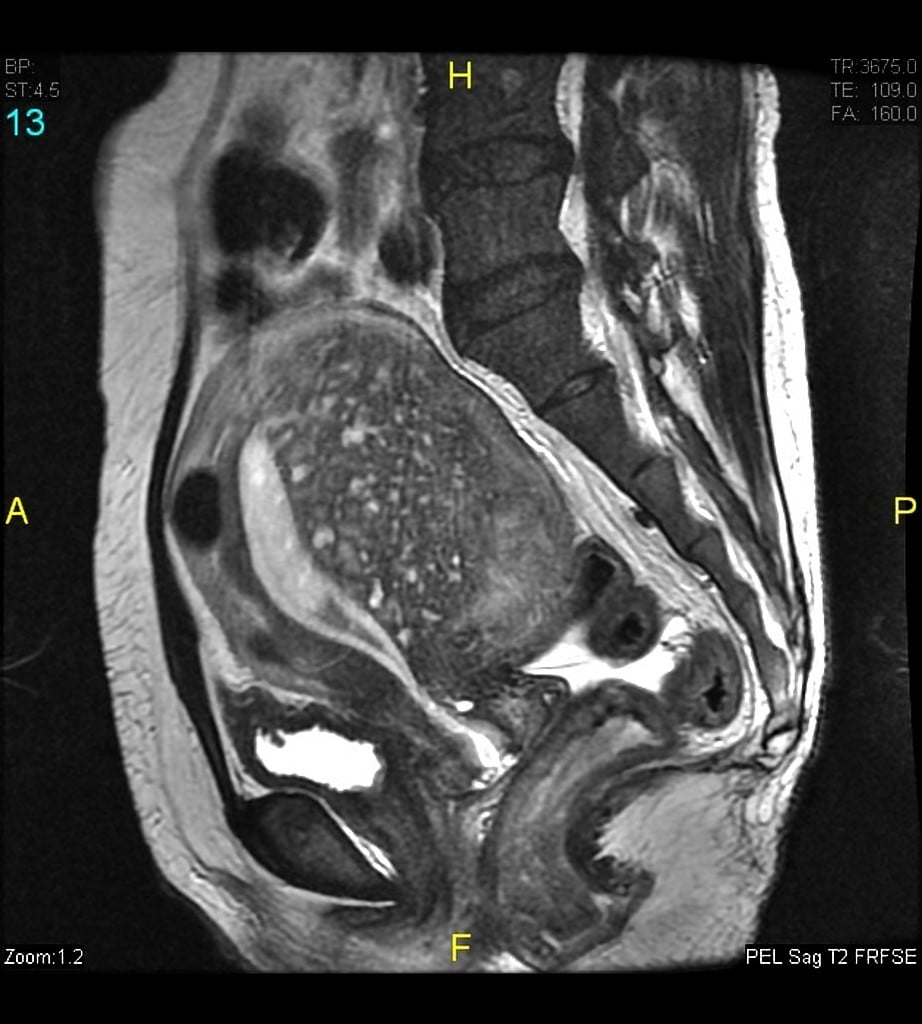

Imagem de ressonância magnética demonstrando adenomiose localizada na parede posterior do útero. Imagem do Dr Varun Babu, Radiopaedia.org. https://commons.wikimedia.org/w/index.php?curid=54052786